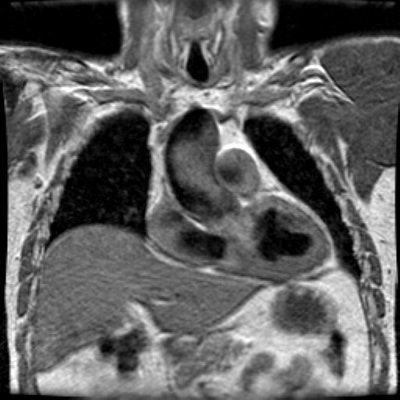

There is prominence to the ascending aorta seen on the coronal image. The patient was found to have a bicuspid aortic valve and this is likely related to post-stenotic dilatation of the ascending aorta.

Flow images reveal signal void in the descending aorta at the level of stenosis consistent with turbulent flow. Some signal void is also noted in the ascending aorta- likely related to the bicuspid valve.